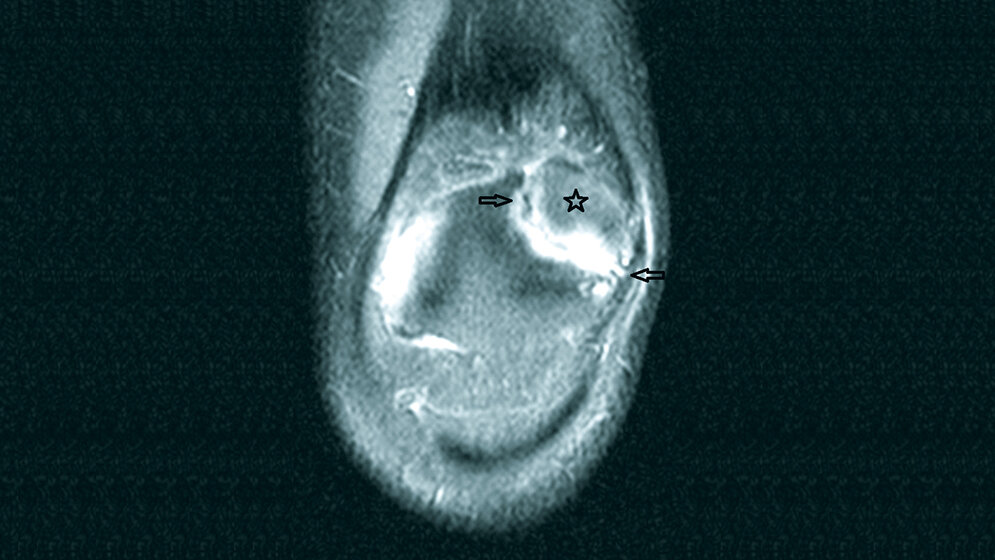

Die Patella bipartita ist eine nicht selten vorkommende Veränderung bei etwa 2–3 % der Population. Meist tritt sie beidseitig auf und ist asymptomatisch. In den meisten symptomatischen Fällen verursacht die Beweglichkeit zwischen der Patella und dem isolierten Fragment die Schmerzen. Die Indikation zur chirurgischen Behandlung einer Patella bipartita sollte nicht vom Ergebnis der Skelettszintigraphie abhängig gemacht werden.

Patella bipartite is a common pathology, affecting 2 % to 3 % of the population. Usually these cases are bilateral and asymptom-atic. In most symptomatic cases, movement at the interface between the bipartite fragment and the body of the patella presum-ably the pain. Surgical treatment should not be considered based only on scintigraphic findings.